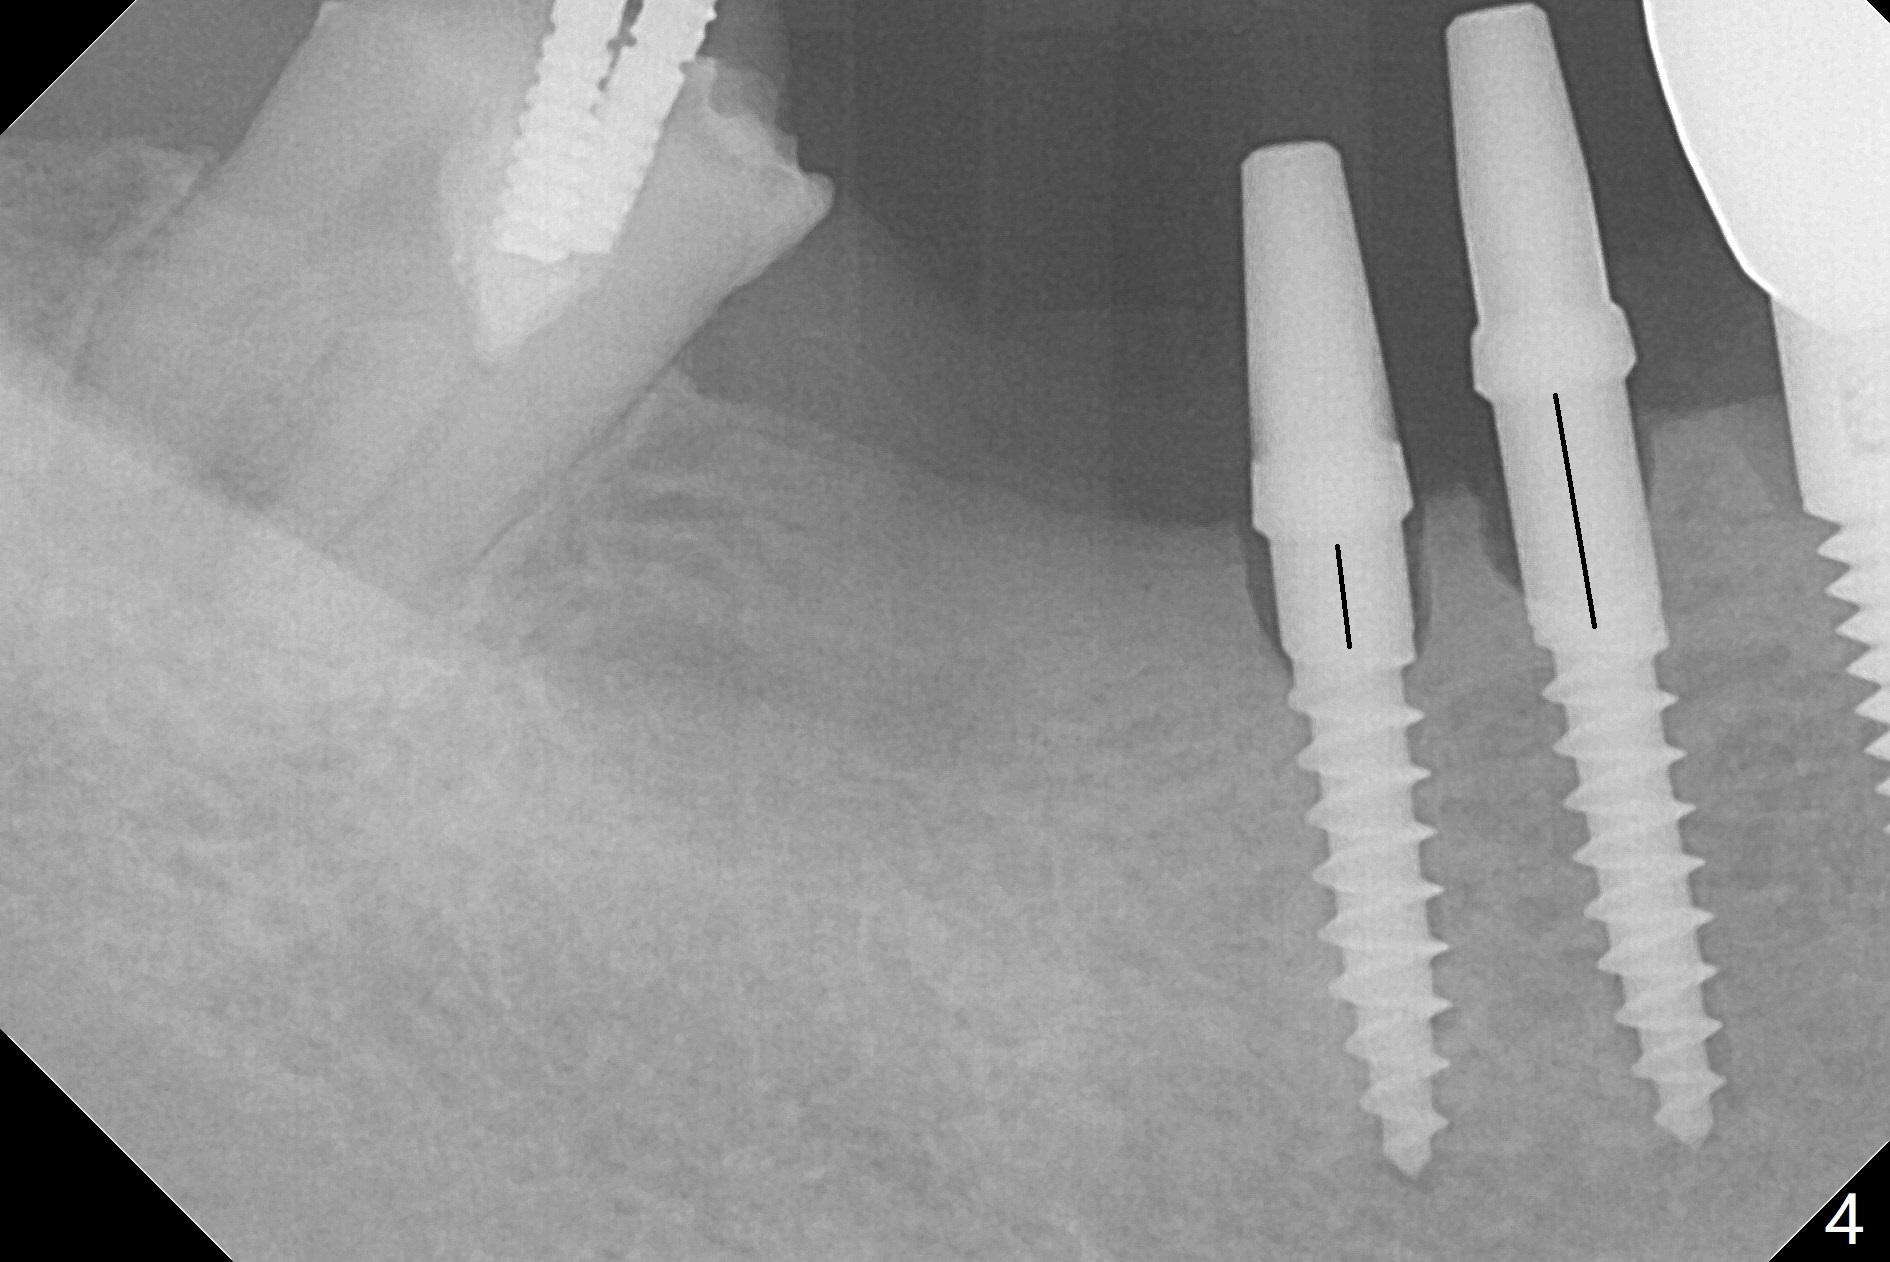

Two of 2.5 mm 1-Piece Implants M

The edentulous ridge at #30 is narrow (Fig.1). After ridge reduction, osteotomy is initiated with 1.2 mm drill for 10 mm; the mesial osteotomy is to be changed (Fig.2 red line). Using a 1.2 mm drill placed in the distal osteotomy (Fig.3 D), the mesial osteotomy changes in trajectory with subsequent placement of a 2.5x10(4) mm 1-piece implant. Since the mesial implant is high in occlusion, the cuff of the distal implant is changed to be 2 mm (Fig.4 (shorter black line)). Panoramic X-ray is taken to show no violation of the Inferior Alveolar Canal (Fig.5 red dashed line). These two 1-piece implants are slightly lingually placed (Fig.6). The crestal bone around the implants resorbs without thread exposure 5 months postop (Fig.7). Impression is taken for a splinted crown (Fig.8-12). There is no metal show around the 2.5 mm 1-piece implants 6 months postop (advantage) vs. that at #28 and 29 (Fig.13). Bitewing is taken post cementation to determine whether residual cement is present (Fig.14). There is periodic swelling and pain in the lower right quadrant 2 years post cementation (Fig.15). In fact periimplantitis appears to have developed at #28 (Fig.16) with loss of the buccal bone (Fig.17,18). The buccal bone loss is less at #29 (Fig.19) and #20 (Fig.23) and no at #30 mesial and distal implants (Fig.20,21). A much smaller implant will be placed lingually at #28 immediate (Fig.24,25).